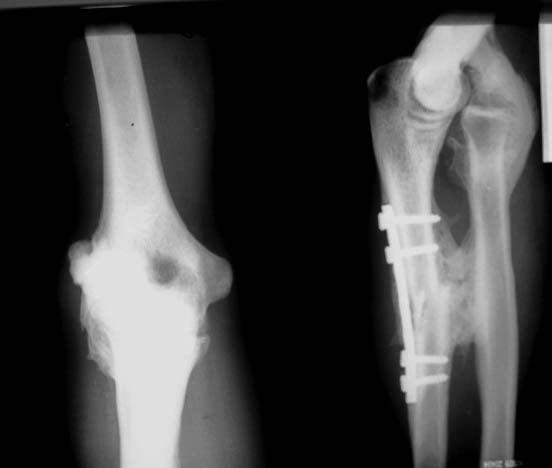

Добрый день, на сколько мне кажется, вправлять головку луча нет смысла, окружающие ткани сильно кальцинированы, так что думаю, что объем следующий: резекция головки луча с кальцинатом, удаление пластины с томией синостоза.

В плане лечения неправильно сросшийся перелом не даст репонировать головку. Значит надо делать остеотомию локтевой кости с хорошей чисткой мозоли. Доступ - задне-латеральный по Boyd-у, но не представляю как удастся очистить головку от мозоли и репонировать. А фиксировать по-новому локтевую кость только с репонированной головкой. Может тогда и достигнется какое-то движение в суставе.

Кисть в достаточно функциональном положении. Планирую все-таки первым этапом ограничиться резекцией головки по возможности гетеротопического экзостоза. Если удастся восстановить сгибание, вторым этапом удалим фиксатор и лочелоктевой синостоз

Резекция экзостозов, вправление вывиха головки, пластика аннулярной связки. Резекция головки лучевой кости чревата проблемами в дистальном радио-ульнарном сочленении. Зачем создавать больному новые проблемы?

Вполне возможно, что придется делать и постеро-латерал/медиал capsular release. Иммобилизация в положении сгибания 90 градусов. По стихании послеоперационных болей начинать с физиотерапии со сменными лонгетами в положении сгибания/разгибания.